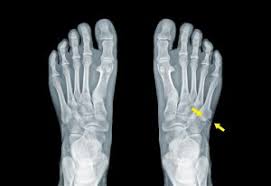

Foot pain is a common ailment among runners and also one that can be confusing because the causes and treatments for the pain can vary widely. Rest, ice, and elevate your foot. There was no cracking or popping when the pain started. The side of foot pain from stress fractures usually starts off quite mild and gradually gets worse. Pain on the outside of the foot (side of the pinky toe) is a common problem we treat in our seattle foot and ankle clinic. The foot is a complicated anatomical structure that carries the weight of the body, and pain can manifest in different ways depending on the cause. Several things can cause lateral foot pain, from exercising too much to birth stiffness and pain in your feet, especially near the back and sides, that feels sharper after a lot of physical activity. Not all foot pain is serious, but you should never ignore any aches. For about two months now i have had this sharp and achy pain on the outer edge of my left foot. Pain on side of right foot and ankle. The pain may be on the inner side of the foot (medial foot pain) or on the outer side (lateral foot pain). There are 3 very common regions for pain on the side of your foot. If you have pain on the side of the foot, whether on the inside or outside, one of the causes can be tendinitis (nflammation of a tendon) or a stress fracture.

Call 206.344.3808 or use our patient portal to schedule an appointment for an evaluation and treatment. Nerve root irritation or compression in the lumbar or sacral spine (lower back) may cause sciatica pain to radiate down your leg and into the foot.1 specifically, compression of the s1 nerve root, also called classic sciatica, can cause pain along the outer side of. Outer side of foot pain) but it frequently goes undiagnosed which can lead to symptoms being present for long periods. Cuboid syndrome is a less common cause of lateral foot pain (i.e. Not all foot pain is serious, but you should never ignore any aches. Thinking it was a sprain i rubbed some ointment and after two weeks the swelling has gone down but i still walked with a slight pain to the. There are 3 very common regions for pain on the side of your foot. If you have pain on the side of the foot, whether on the inside or outside, one of the causes can be tendinitis (nflammation of a tendon) or a stress fracture. If there is friction, compression and rubbing over the skin, this can impinge the nerve. Ask your doctor if surgery is necessary. If you experience the pain on outer side of foot around the heel, the likely cause may be peroneal tendonitis. Pain on side of right foot and ankle. The seriousness of such pain can range from mild to moderate to severe.